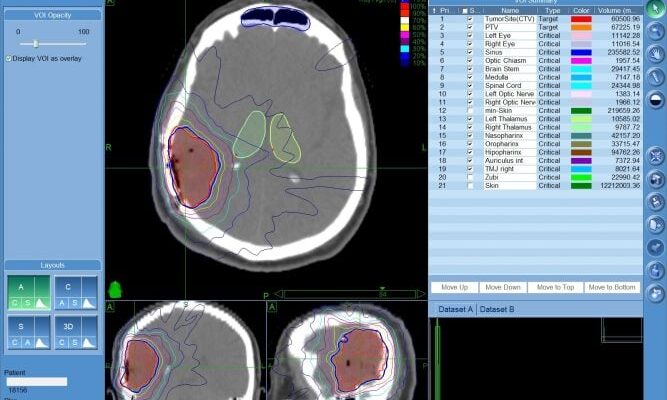

3. Променева терапія

Інша зброя арсеналу — променева гармата. Госпітальний апарат опромінює уражену зону. Пацієнт відчуває, наче його нейрони прожарюють в мікрохвильовці.